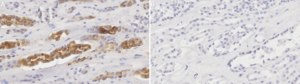

Immunohistochemistry (Paraffin) Analysis: A 1:100 dilution from a representative lot detected EGF in human kidney tissue sections.